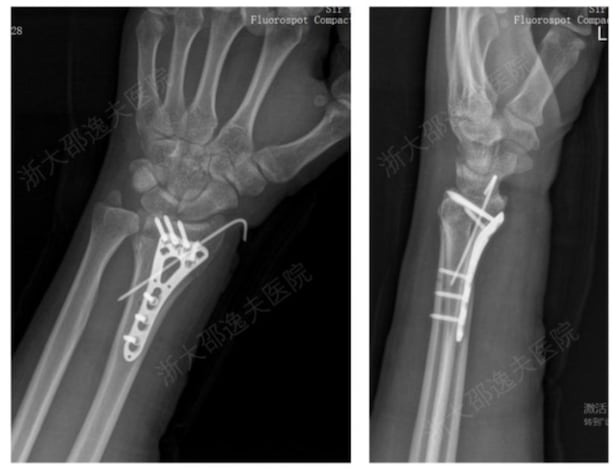

기존 금속 고정으로 손목 골절을 치료한 모습./CCTV 캡처

접착제 치료로 손목 골절을 치료한 모습./CCTV 캡처